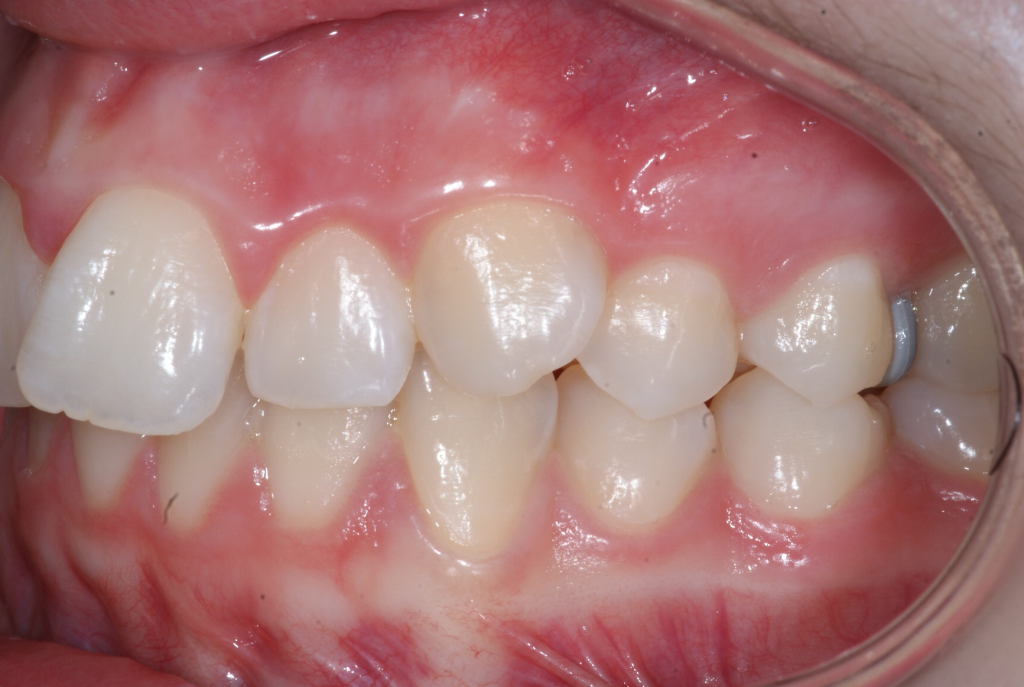

Correction d’une malocclusion de type Classe II division 1, surplomb horizontal inadéquat et chevauchement modéré aux 2 arcades. Des appareils fixes (broches et vis d’expansion) et des élastiques furent nécessaires pour améliorer ce sourire. Traitement chez une adolescente, réalisé en 18 mois.